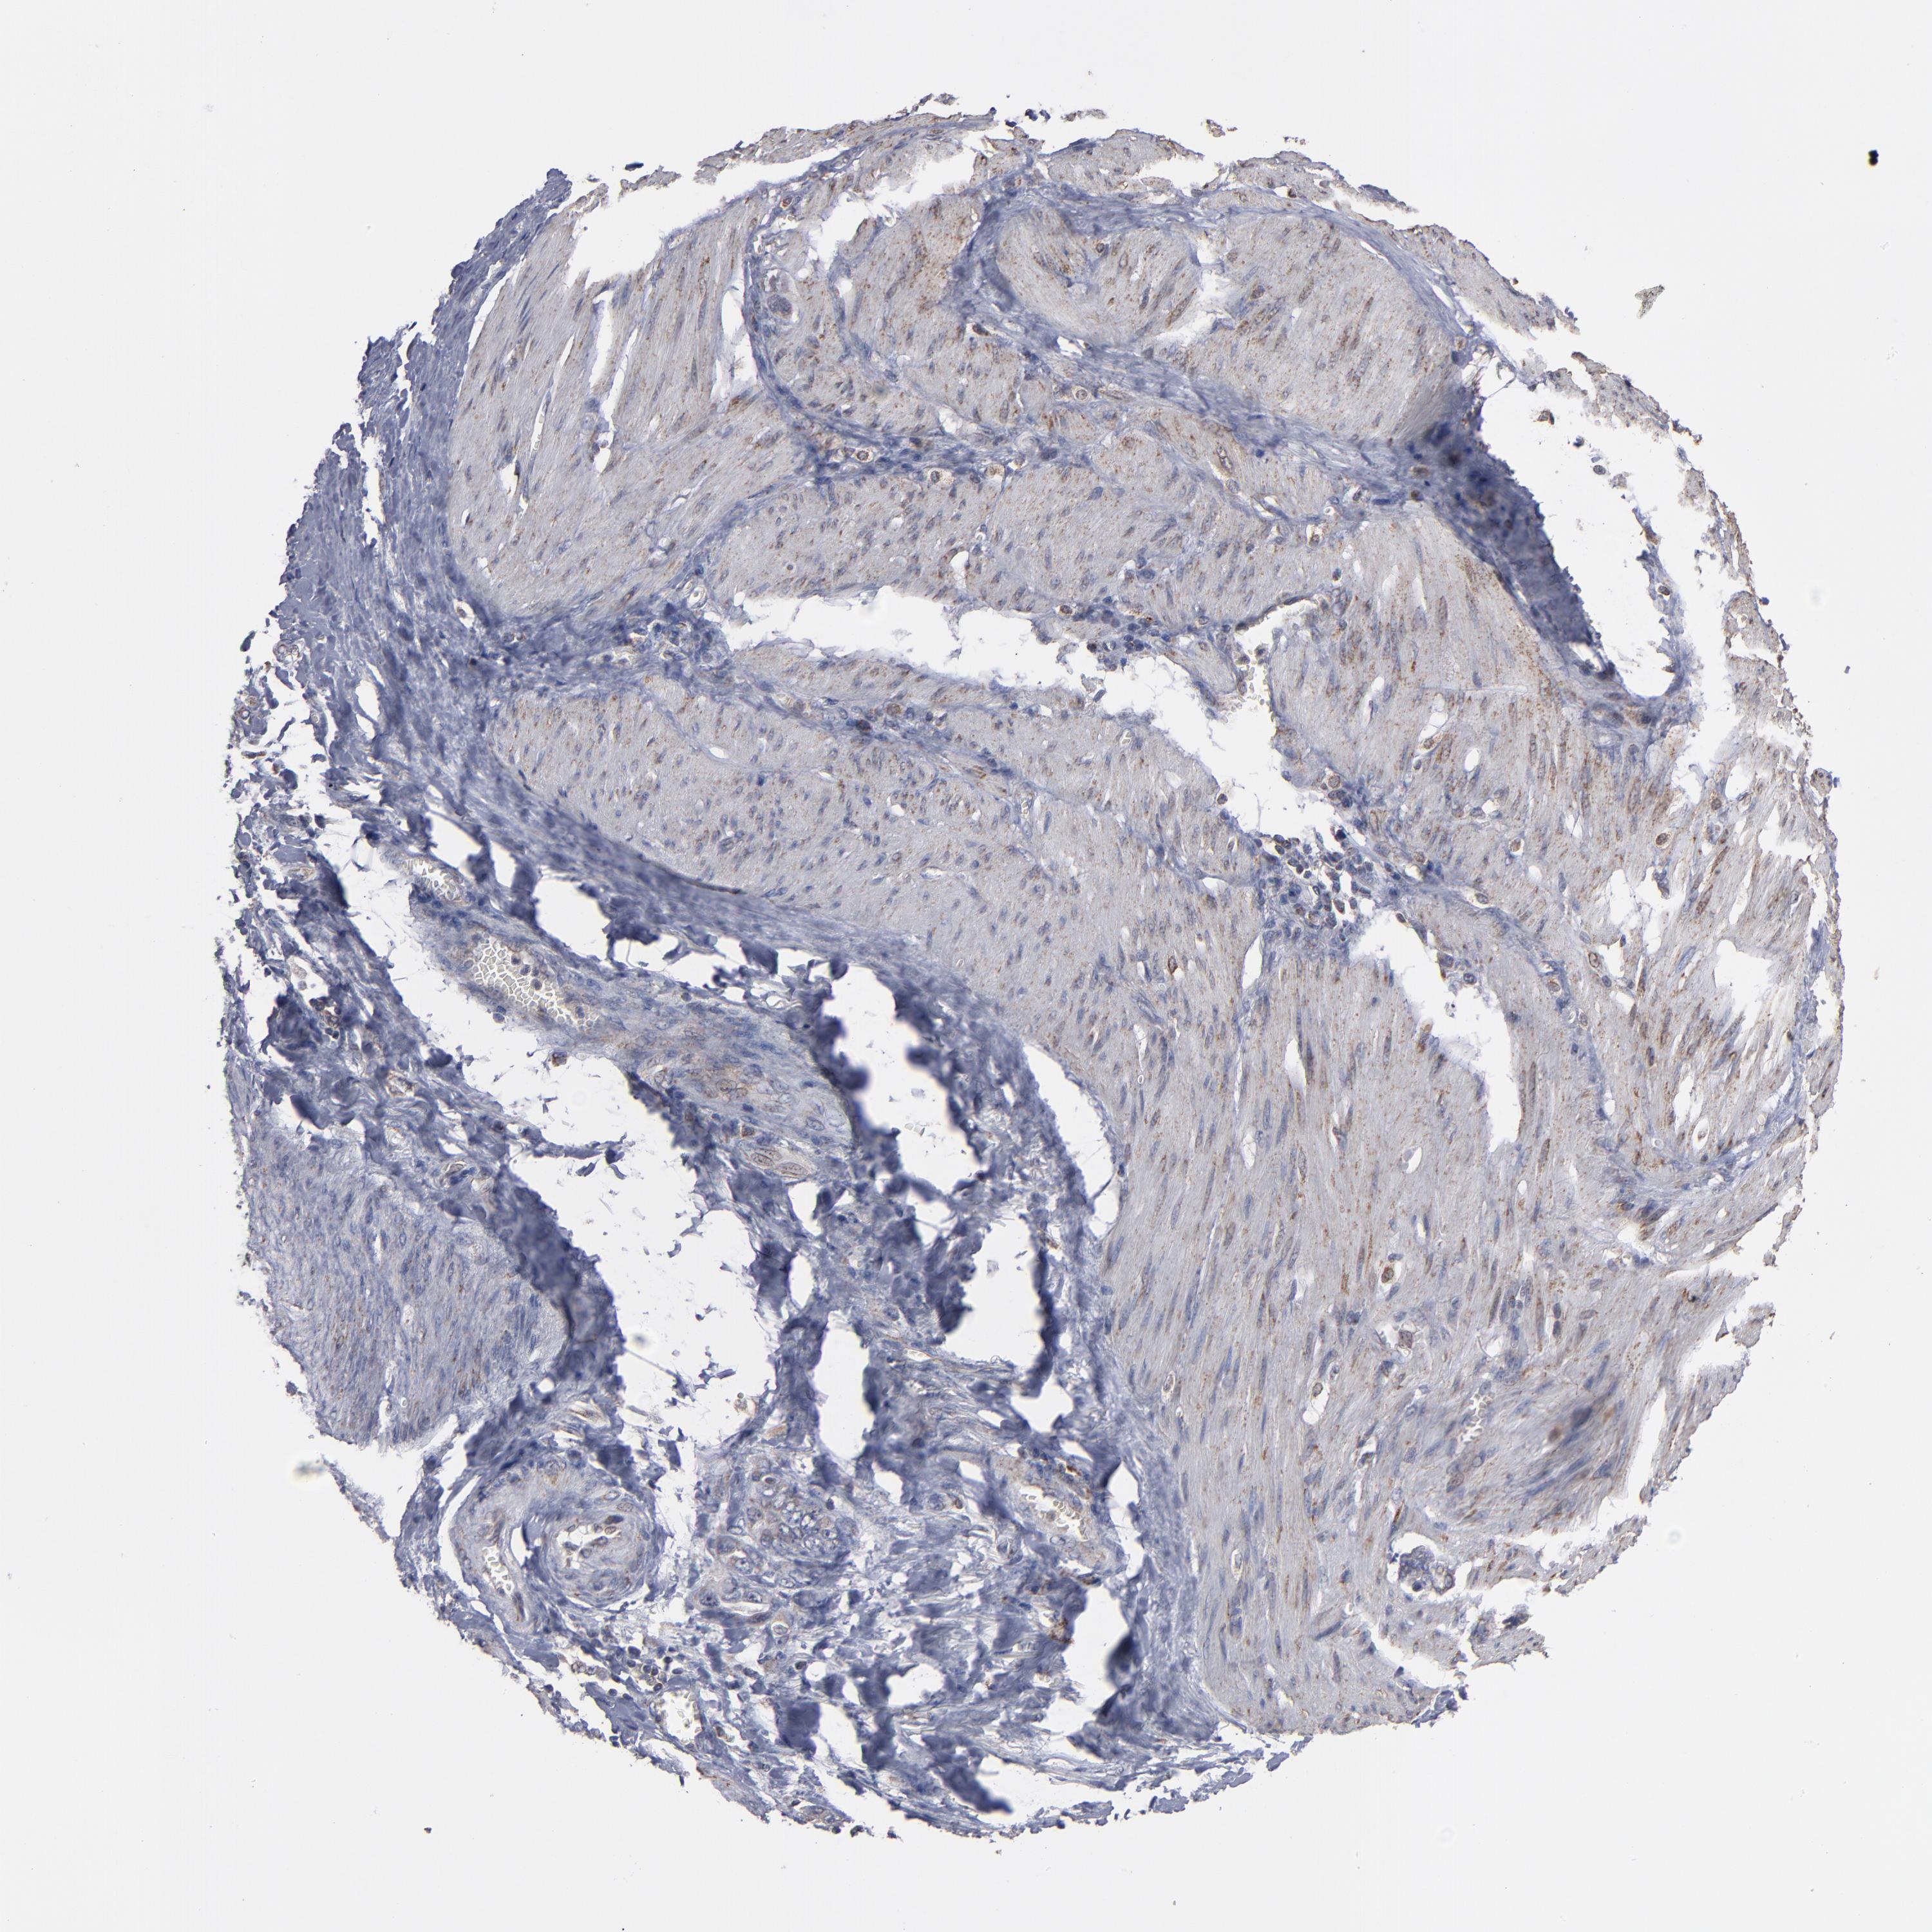

STOMACH CANCER - Protein expressioni

A mouse-over function shows sample information and annotation data. Click on an image to view it in a full screen mode. Samples can be filtered based on level of antibody staining by selecting one or several of the following categories: high, medium, low and not detected. The assay and annotation is described here.

Note that samples used for immunohistochemistry by the Human Protein Atlas do not correspond to samples in the TCGA dataset.

Antibody stainingi

Antibody staining in the annotated cell types in the current human tissue is reported as not detected, low, medium, or high, based on conventional immunohistochemistry profiling in selected tissues. This score is based on the combination of the staining intensity and fraction of stained cells.

Each image is clickable and will lead to virtual microscopy that enables deeper exploration of all samples and also displays staining intensity scores, fraction scores and subcellular localization as well as patient and tissue information for each sample.

Antibody HPA002893

Staining

High

Medium

Low

Not detected

Intensity

Strong

Moderate

Weak

Negative

Quantity

>75%

75%-25%

<25%

None

Location

Nuclear

Cytoplasmic/membranous

Cytoplasmic/membranous,nuclear

Adenocarcinoma, NOS